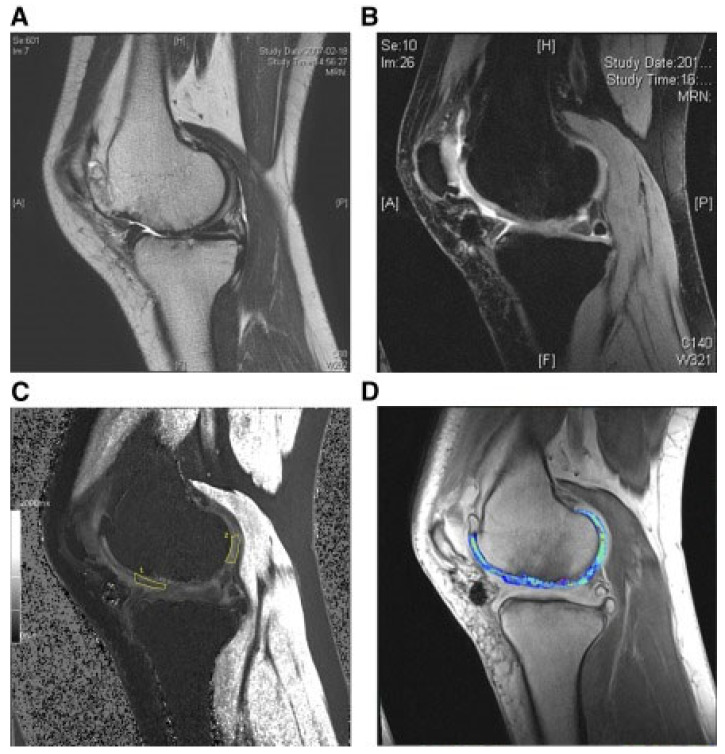

人臍帶血來源的間充質干細胞治療關節炎

還評估了人臍帶血來源的間充質干細胞(HUCB-MSC)治療軟骨再生的安全性和有效性。根據國際軟骨修復協會的數據,HUCB-MSC用于治療7名患有KLIII級OA和IV級軟骨缺損的患者。同種異體HUCB-MSC在體外生長,然后與HA水凝膠結合并應用于損傷部位。微骨折方案與這些細胞結合使用。12周后,修復的組織似乎成熟,24周后,臨床評分增加。在整個7年隨訪過程中,臨床改善的穩定性也值得注意。組織學用于在手術后一年顯示透明軟骨,而MRI用于在手術后3年顯示軟骨再生,如圖所示圖3(其中釓-DTPA用作造影劑,以藍色顯示)。

圖3:HUCB-MSC治療后3年軟骨再生的MRI評估

(A) 術前軟骨缺損。(B) 移植后3年軟骨再生。(C) 通過在標記區域采樣來計算相對軟骨松弛率的變化。(D) 顯示與藍色信號相關的GAG含量增加。